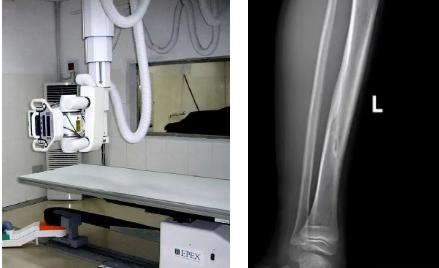

一般骨科創(chuàng)傷的病人,只要到影像科拍一張X光片,很快就會(huì)明確診斷有沒(méi)有骨折。然而有一些特殊類型骨折的病人,由于拍片影像重疊的緣故,或者骨折未發(fā)生明顯移位,病變可能顯示不出來(lái),等過(guò)了一段時(shí)間后,骨折部位才能夠顯示清楚。這種類型的骨折,叫做隱匿性骨折。若在臨床上診斷及時(shí)且明確,及時(shí)固定患者的骨折部位,進(jìn)行適當(dāng)治療并減少運(yùn)動(dòng),對(duì)患者的恢復(fù)有重要意義。

1.定期復(fù)查。一般于骨折后2-4周,骨折進(jìn)入骨痂期,骨折斷端有新生骨形成,呈明顯高密度,無(wú)論是X線或是CT,都能比較清晰觀察到,通過(guò)前后圖像對(duì)比,較容易診斷隱匿性骨折。

2.CT或MRI檢查。CT是斷面成像,不會(huì)出現(xiàn)重疊而導(dǎo)致漏診,同時(shí)CT還可以進(jìn)行多平面的重建,除了發(fā)現(xiàn)X線無(wú)法發(fā)現(xiàn)的骨折外,還可以三維直觀的顯示骨折的程度,對(duì)臨床治療有指導(dǎo)意義。CT無(wú)法發(fā)現(xiàn)骨裂、不全骨折或者骨挫傷,對(duì)軟組織的損傷診斷也有局限性,MRI就可以發(fā)現(xiàn)這些損傷。